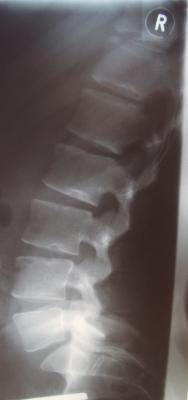

- Hyperlordose korrigiert von 78° auf 39°

Kyphose von 19° auf 14°

Nicht mehr aus dem Lot - Ganzaufnahme-im-Korsett.jpg (29.45 KiB) 14428 mal betrachtet

Gestern wurde ich im Korsett geröngt. Herr Rahmouni war mit dem Ergebnis sehr zufrieden. Ich bin auf auf Grund des starken Flachrückens jedoch noch ein wenig skeptisch.